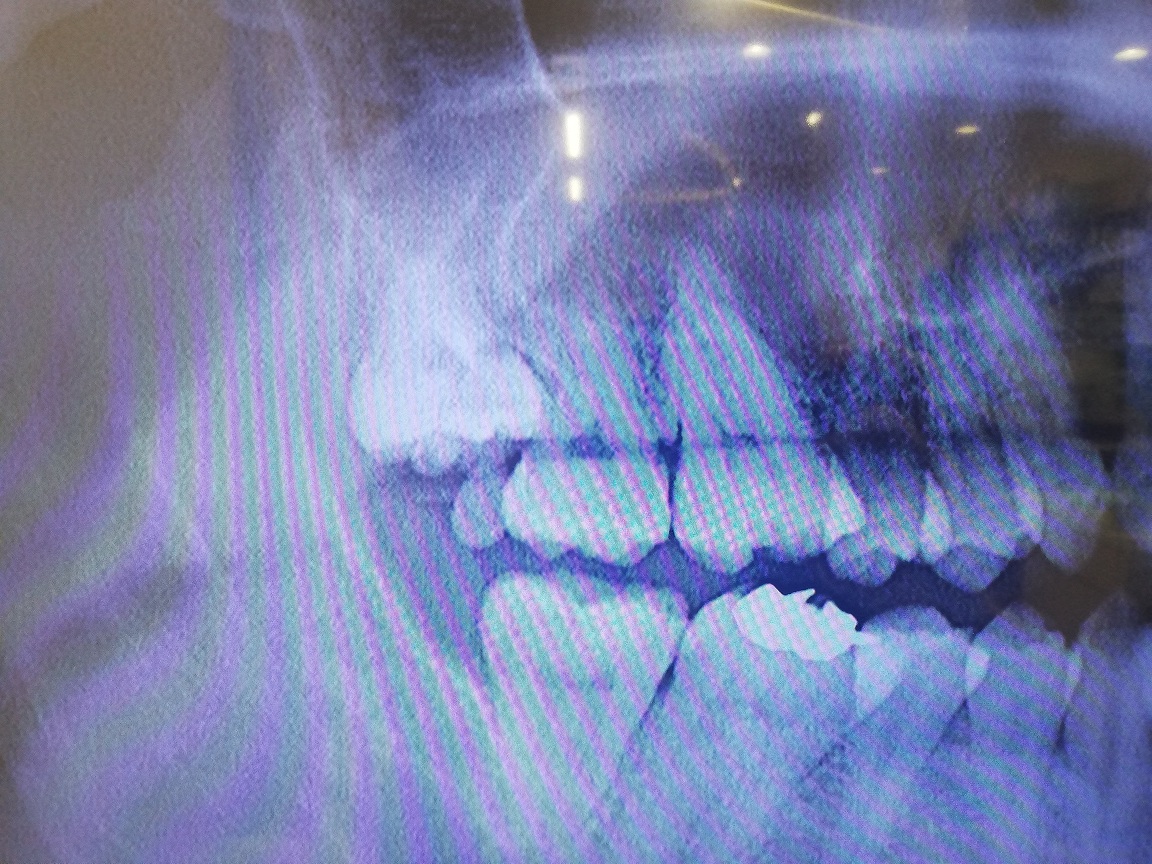

右上の親知らずについて抜いてもらおうと思いCTを撮影してもらったところ、親知らずが隣の歯を支えている状況であり、親知らずを抜くと隣の歯(7番)が揺れる可能性があるとのことでした。

抜歯のメリットは、親知らずの隣の歯を専用のブラシで清掃し管理できるようになることで、デメリットは、親知らずの隣の歯(7番)の寿命を親知らず抜歯によって、かえって縮めてしまう可能性があるとのことでした。

主治医の先生は、通常なら親知らず抜歯を勧める状況だが、わたしの場合は、通常の人よりも副鼻腔が大きく、親知らずの隣の歯(7番)の歯根が歯槽骨に埋まってる長さが少ないために、親知らず抜歯によって7番が揺れるようになる可能性があるとのことでした。さらに、親知らずが7番を支えているような状況だそうで、噛める力が弱くなる可能性もあるとのことでした。

添付の画像は、問題の親知らずのレントゲン写真とCT画像になります。

画像1右上親知らず.jpg 画像2右上親知らずCT.jpg

普段見かけないものが7番は8番の間にあるように思いますがいかがですか?

このようなケースの場合ごく稀に7番の遠心側が外部吸収していることがあります。その場合には7番を抜歯して8番を矯正治療で7番の位置に移動させられる矯正専門医はたくさんいらっしゃると思います。

また親知らず(8番)があると左側の大臼歯が抜歯になった時のドナーとして使える可能性があると思います。